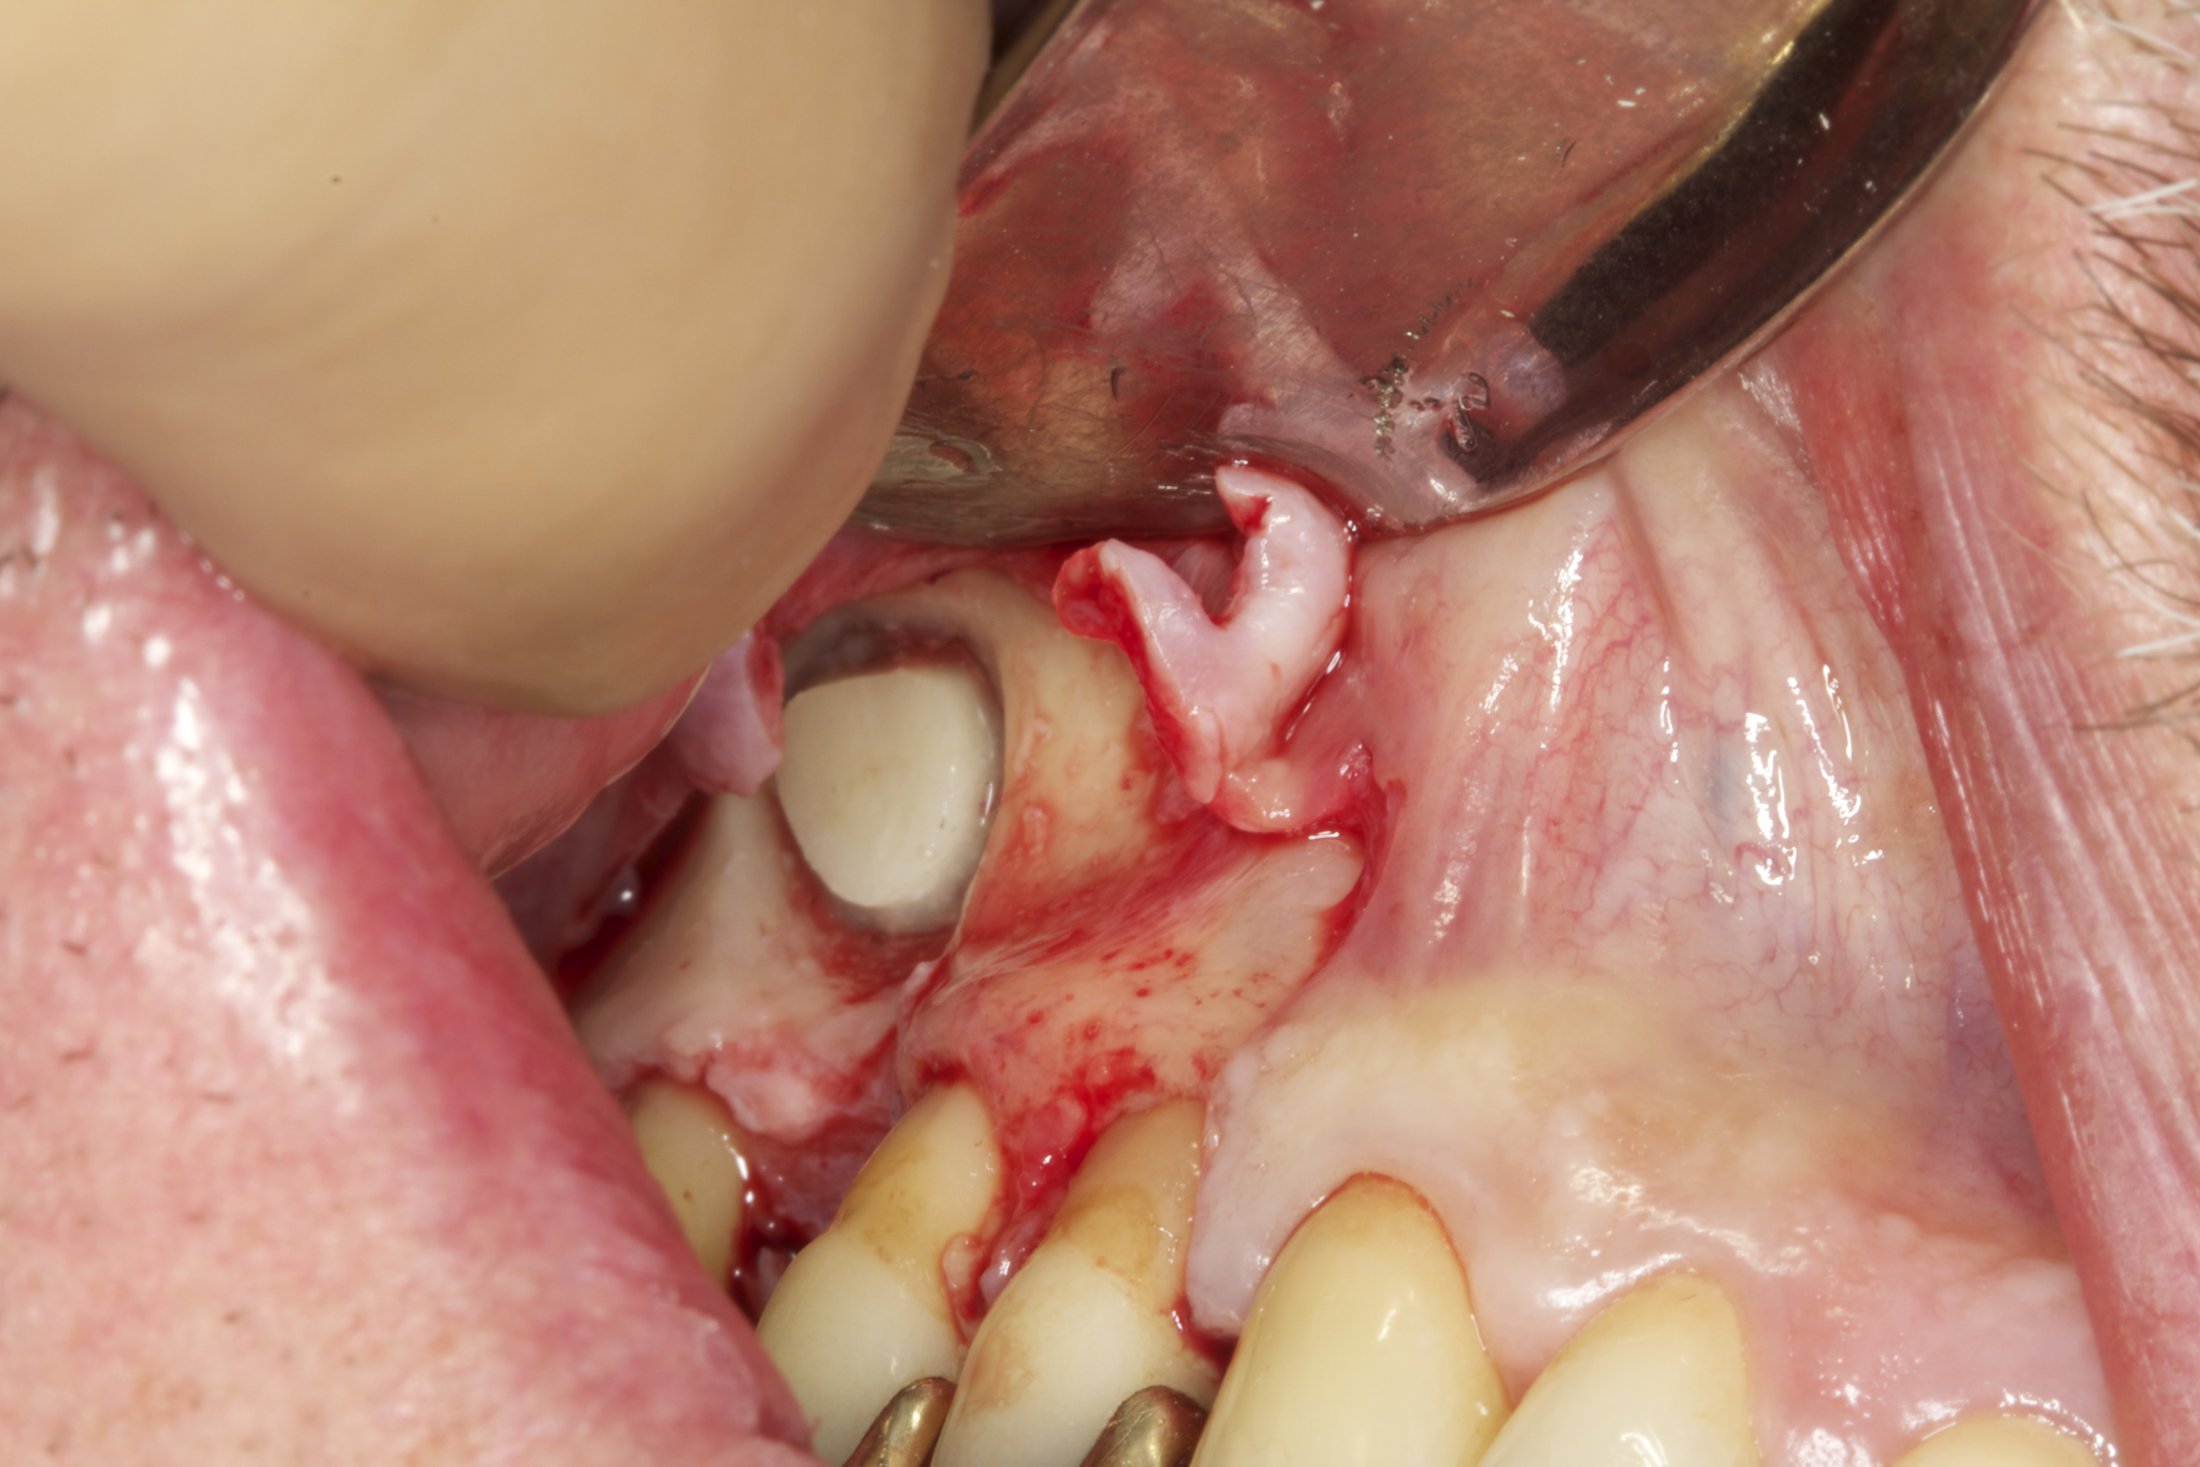

Your surgeon will cut the gum tissue where your back teeth used to be. The tissue is raised, exposing the bone. A small, oval window is opened in the bone. The membrane lining the sinus on the other side of the window separates your sinus from your jaw. This membrane is gently pushed up and away from your jaw.

Granules of bone-graft material are then packed into the space where the sinus was. The amount of bone used will vary, but usually several millimeters of bone is added above the jaw.

Once the bone is in place, the tissue is closed with stitches. Your implants will be placed four to nine months later. This allows time for the grafted material to mesh with your bone. The amount of time depends on the amount of bone needed.